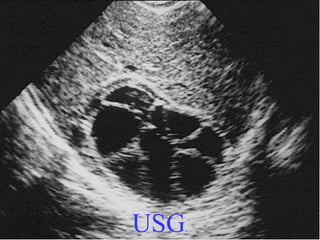

USG.

Diagnostic Studies • LaboratoryTests • Imaging – X-ray – USG – CT – MRI – Nuclear Scan • Other Tests